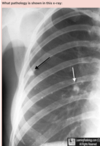

**Answer: Ranke complex** ## Footnote There is a combination of a calcified peripheral granuloma (black arrow) and a calcified hilar lymph node (white arrow) on the same side. Several other, small calcified granulomas are seen in the right mid-lung field. A “Ghon Lesion” or focus is a granuloma in the lung from a previous tuberculous infection. It is a sequela of primary tuberculosis When there is a combination of a parenchymal granuloma and an involved hilar lymph node on the same side, the two together are called a “Ghon Complex” The combination of late fibrocalcific lesions of the lung and lymph node which evolved from the Ghon complex is referred to as the “Ranke complex”